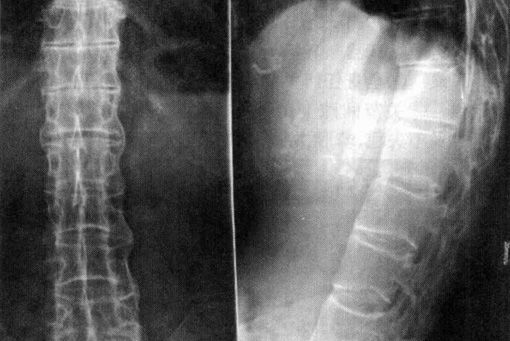

强直性脊柱炎

QZ16030094 姓名:陈先生 性别:男 年龄:32岁

AS ①晚期 ②重度 病史:5年+

治疗后骶髂关节疼痛消失,腰椎前屈、背伸侧弯活动自如,膝关节无压痛感,复查血沉、C反应蛋白、等各项检查均已达到临床康复的标准。